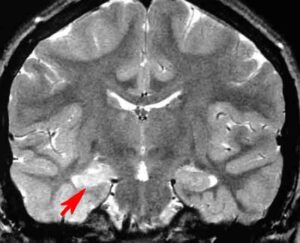

Alcuni ricercatori britannici hanno scoperto un ritardo nello sviluppo infantile nelle sei settimane successive a uno stato convulsivo epilettico (Cse), una crisi che dura per piu’ di 30 minuti. epilessiaLo studio compare sulla rivista ‘Epilepsia’ ed e’ opera dello University College London Institute of Child Health di Londra. La ricerca suggerisce che, anche a distanza di un anno dallo Cse, continua a permanere un problema nel neurosviluppo del bambino. Molti studi hanno mostrato che episodi di Cse avvengono di frequente durante i primi tre ani di vita, un periodo critico nella crescita e nello sviluppo del bambino. “Il nostro studio per la prima volta ha esaminato le funzioni cognitive, linguistiche e motorie nei bambini nell’arco di sei settimane dopo il Cse e fino a un anno dopo questo episodio, per tracciarne lo sviluppo’”, ha spiegato Marina Martinos, a capo del gruppo di ricerca. “Il Cse potrebbe avere un impatto a lungo termine sullo sviluppo attraverso una permanente riorganizzazione delle reti funzionali cerebrali. Una riorganizzazione che potrebbe essere gia’ completata quando viene rilevata per la prima volta nel bambino”, ha concluso.